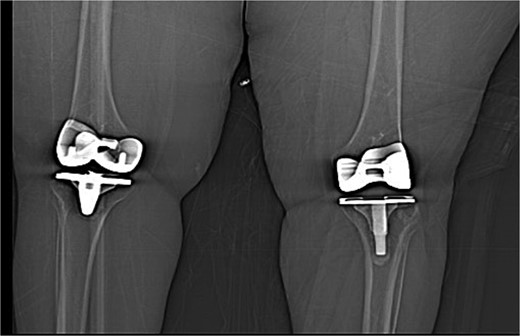

The patient was admitted for investigation. Routine radiographic imaging was unremarkable. Magnetic resonance imaging (MRI) and computed tomography scans were conducted and revealed no abnormalities (Figs 3 and 4). Afterward, the patient was examined under anesthesia, where a stable joint was noted with full knee ROM. The only remarkable finding was the clicking sound with flexion. The impression was that there was polyethylene wear due to the significant weight gain, and the decision was made to discharge the patient with instructions to lose weight and to re-admit electively for TKA revision and possible polyethylene exchange if there was no improvement.

Computed tomography (CT scan) of bilateral knees showing no abnormality.